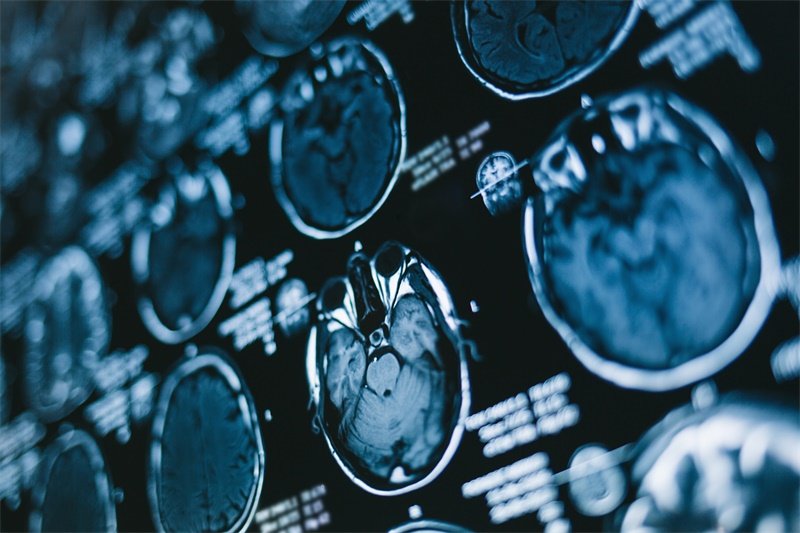

影像学检查

MRI检查:核磁共振成像是判断占位病变性质的最佳手段,尤其是软组织的表现。MRI不仅能确定病变的界限,还能评估其与周围结构的关系。